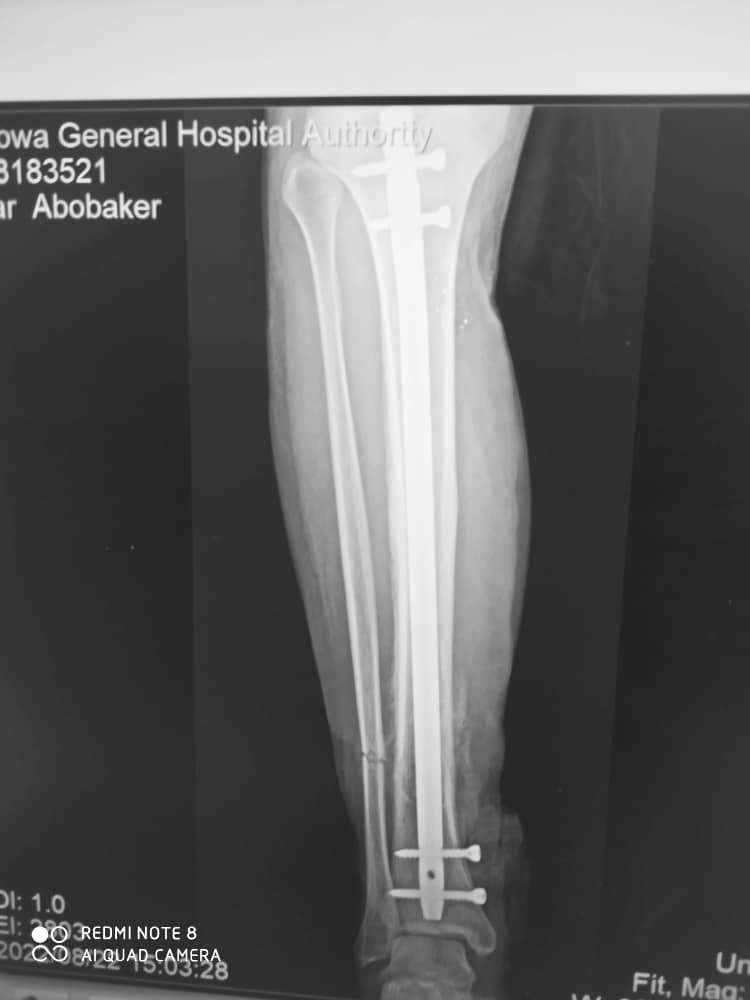

استعاد هيئة مستشفى شبوة العام نشاطه بعد إجراء أعمال الصيانة والترميم بعد التخريب والتدمير الذي طاله أبان الحرب الأخيرة بتمرد مليشيات الإخوان على السلطة المحلية بالمحافظة. حيث يستمر الكادر الطبي في هيئة مستشفى شبوة العام بتقديم خدمات طبية مميزة، فقد تم إجراء عملية تثبيت مسمار نخاع متشابك لمريض يعاني من كسر في عظمة الساق، وهي من أحدث التقنيات في جراحة كسور العظام، حيث تسمح للمريض بالحركة مباشرة بعد العملية والعودة إلى الحياة الطبيعية في وقت قياسي. وقد قام بإجراء العملية د/ محسن الشكلية اخصائي عظام، فنيي العمليات فهمي لشرف وصالح كليس.